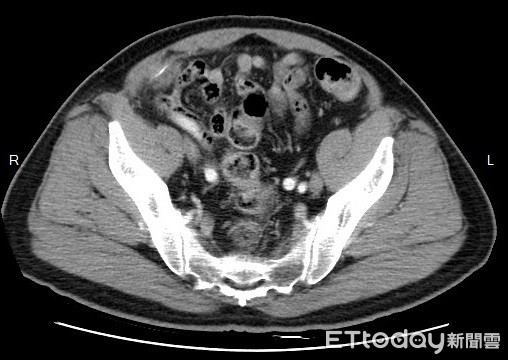

▲男子電腦斷層掃描中有長條狀鐵絲。(圖/謝依蒨醫師提供)

高醫附設醫院大腸直腸外科醫師謝依蒨指出,這名70歲男子近期因為出現肚子痛、發燒等情形,但都一直檢查不出原因,後來透過電腦斷層掃描,發現右下腹影像中出現一團異物,異物內還包著一條長形鐵絲,長達2.5公分,如果不趕緊處理,恐怕會因併發腹膜炎而喪命。